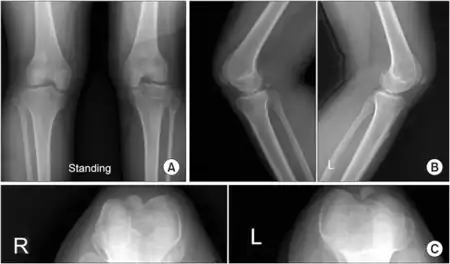

Individuals affected by ischiopatellar dysplasia commonly have abnormalities of the patella and pelvic girdle,[5] such as absent or delayed patellar and ischial ossification as well as infra-acetabular axe-cut notches.[6][7][8] Patellae are typically absent or small in these individuals, when patellae are present they are small and laterally displaced or dislocated.[9] In addition, abnormalities in other parts of their skeleton and dysmorphic features are common in those affected.[10][11] Other features that have been identified in patients with ischiopatellar dysplasia include foot anomalies,[12] specifically flat feet (pes planus), syndactylism of the toes,[13] short fourth and fifth toes, and a large gap between the first and second toes,[14][15] femur anomalies,[16] cleft palate,[17] and craniofacial dysmorphisms.[18][19]

Ischiopatellar dysplasia is usually identified through radiographic evidence since its characteristic changes are most notable in radiographic tests that indicate delayed bone age or absent ossification.[25] A full skeletal survey should be performed on any patient that has an absent or hypoplastic patellae since they could potentially have ischiopatellar dysplasia. Magnetic resonance imaging (MRI) is especially helpful in the diagnosis of ischiopatellar syndrome and is recommended when an individual affected by ischiopatellar dysplasia has a traumatic injury to the knee.[26]